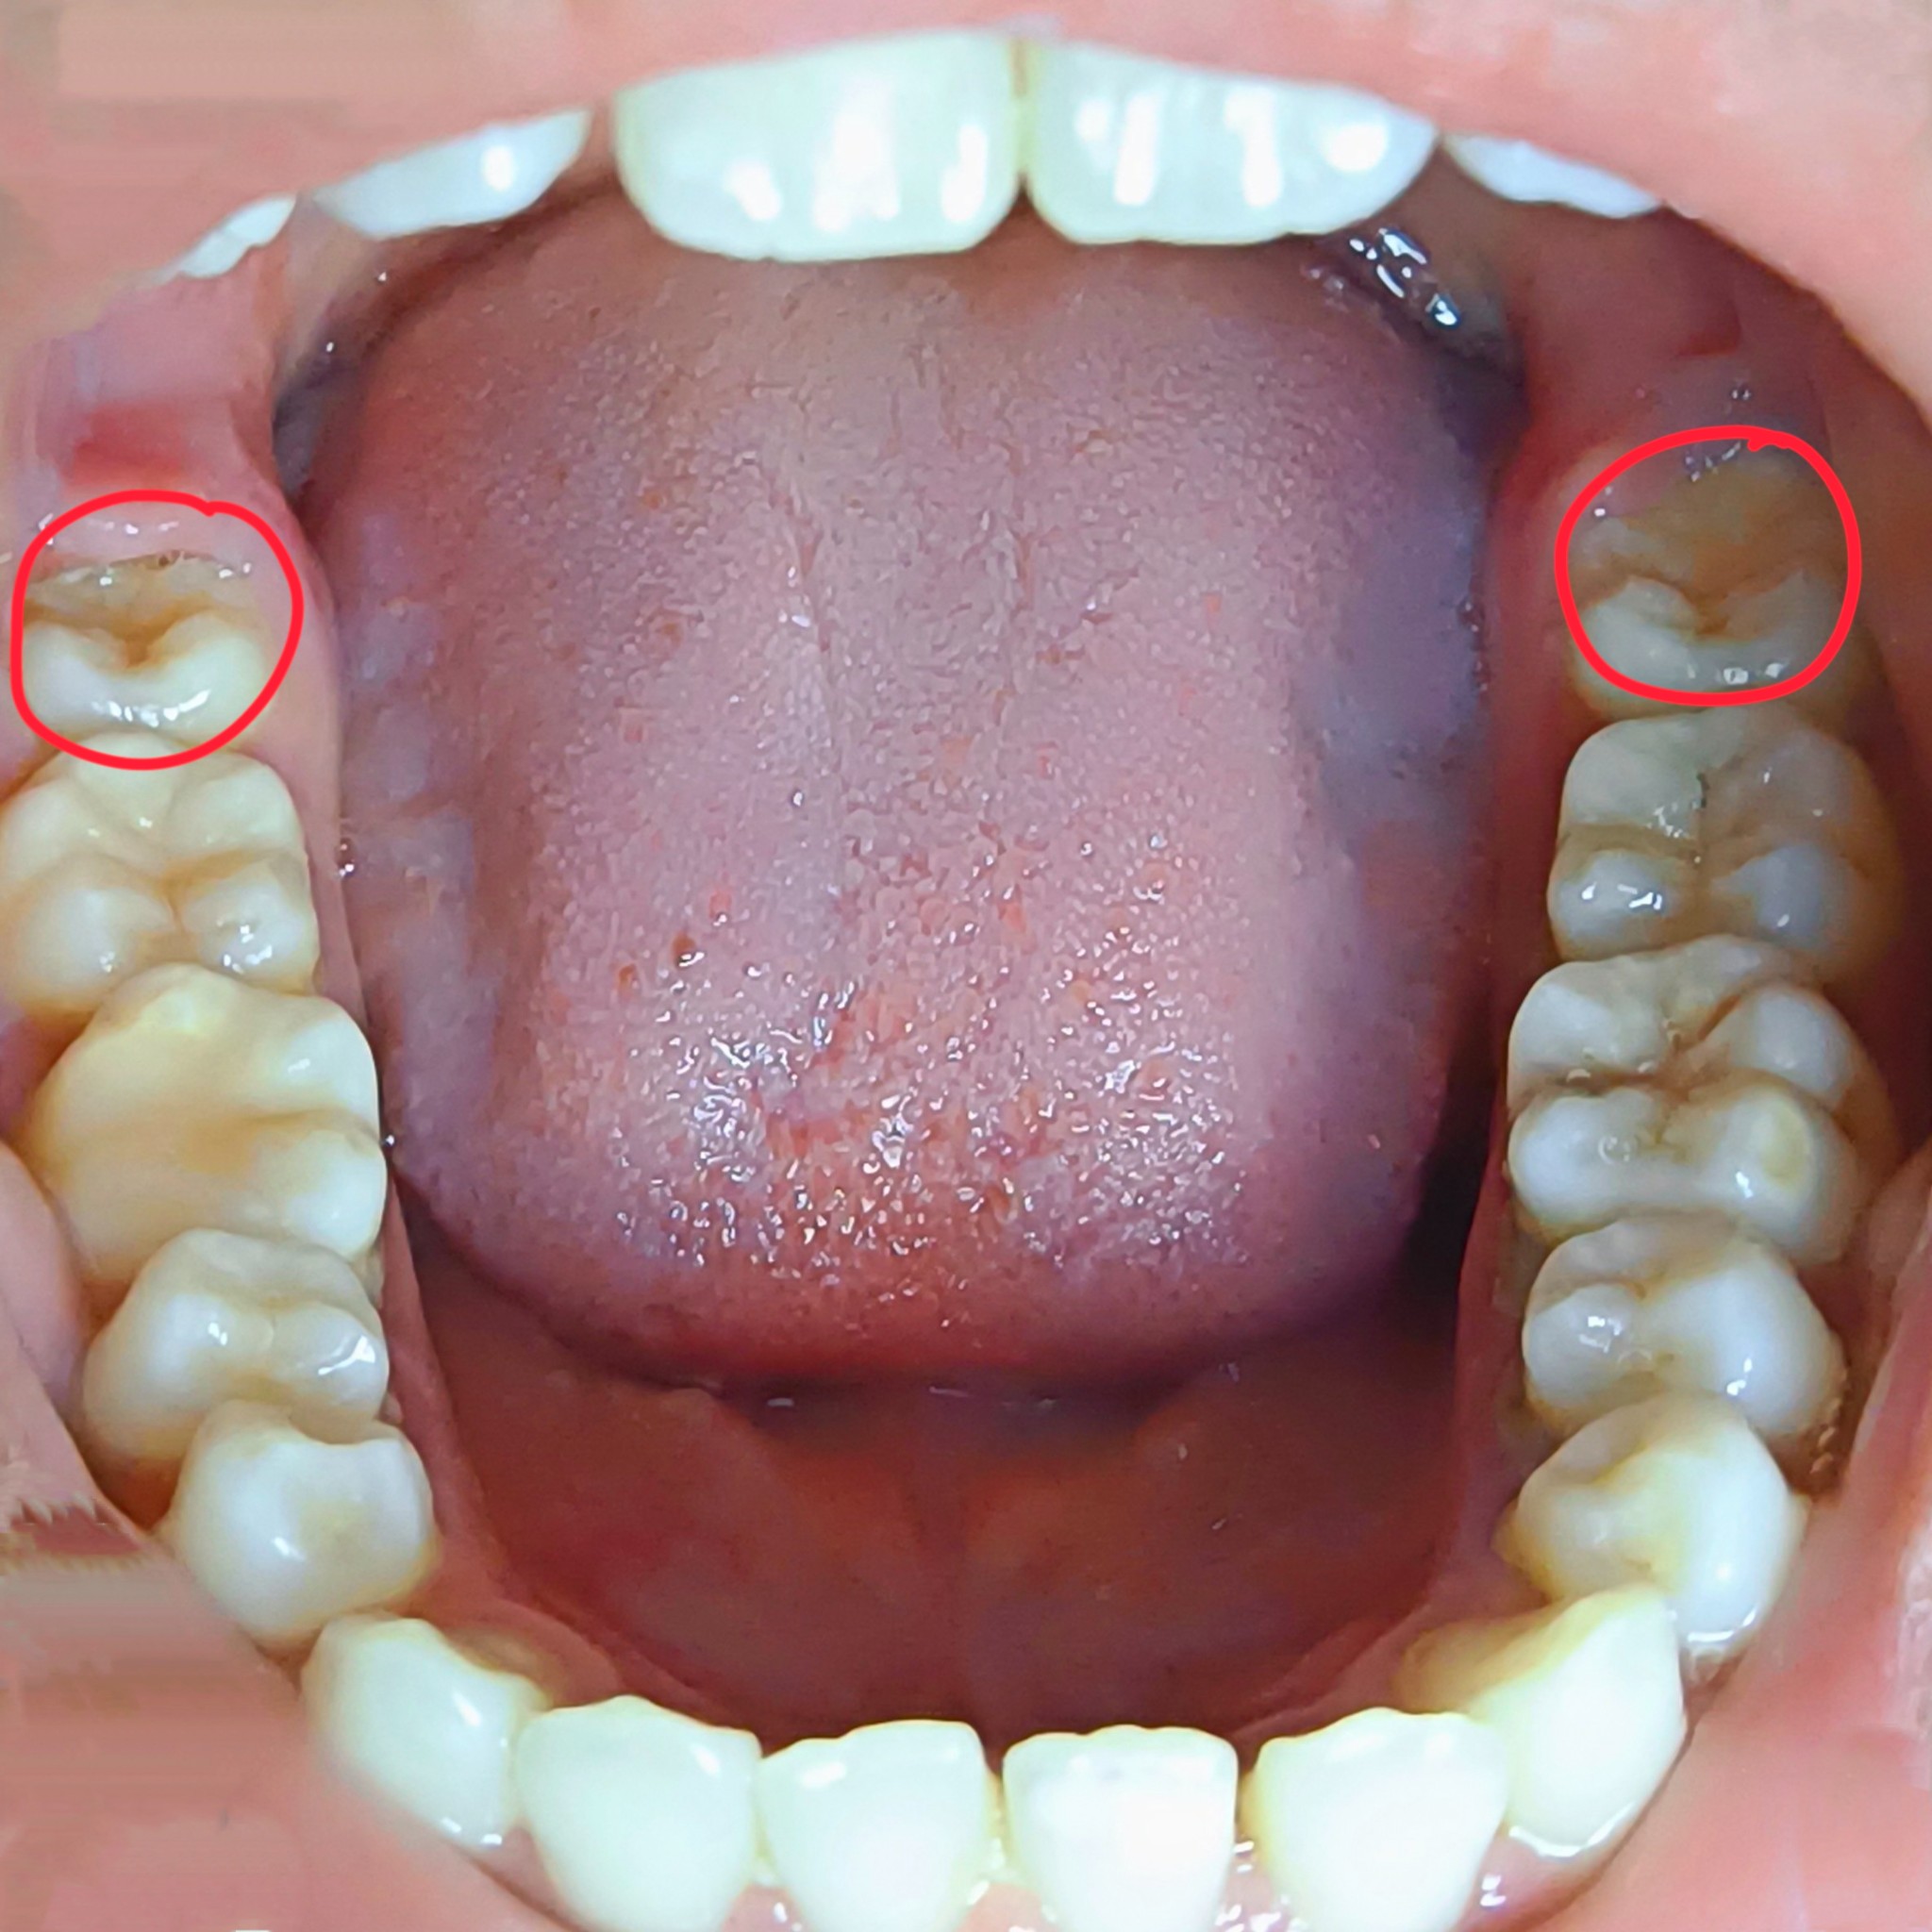

ที่วงกลมสีแดงไว้คือฟันคุดใช่ไหมคะ?

สวัสดีค่ะ อยากทราบว่าฟันซี่ที่วงกลมสีแดงไว้คือฟันคุดหรือเปล่าคะ ตอนนี้มีอาการเหงือกบวมและปวดฟันมากๆ แต่ไม่แน่ใจว่าฟันคุดคือซี่ที่วงไว้ซึ่งขึ้นพ้นเหงือกเกือบหมดแล้ว หรือมีอีกซี่อยู่ถัดไปด้านใน หากที่วงไว้คือฟันคุดแบบนี้ต้องถอนหรือผ่าคะ